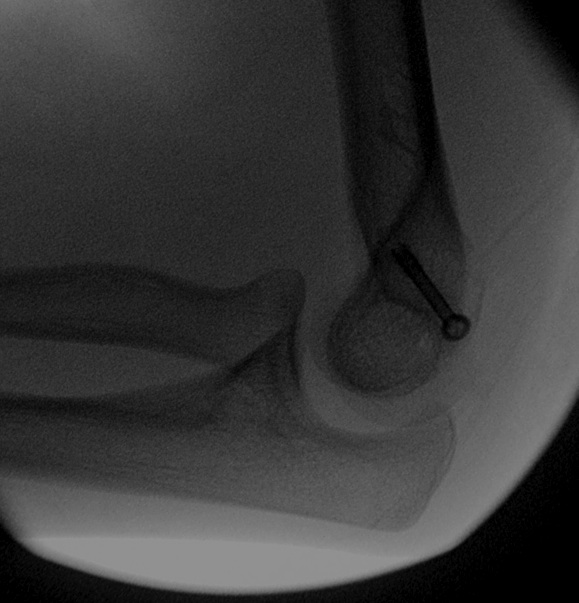

From www.orthobullets.com

Elbow Stiffness and Contractures Shoulder & Elbow Orthobullets Elbow Flexion Contracture Physical Therapy Elbow flexion contracture is the most common complication after injury to the elbow. Loss of elbow range of motion is attributed to capsular and. Contracture may develop following traumatic injury such as. Flexion contractures greater than 30° or the inability to flex the elbow to at least 130° is often an indication for surgery. The elbow joint after trauma is. Elbow Flexion Contracture Physical Therapy.